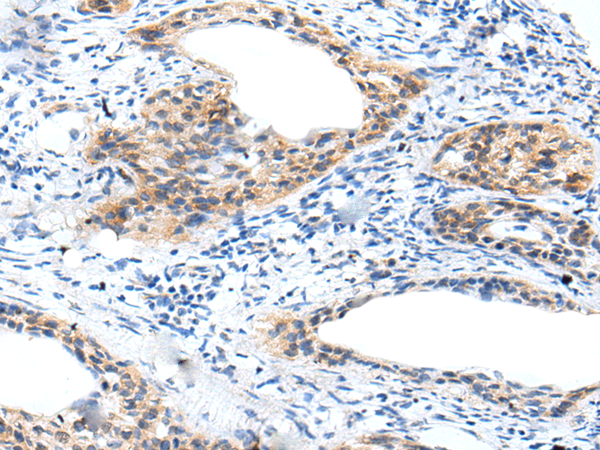

IHC positive control: |

Human cervical cancer |